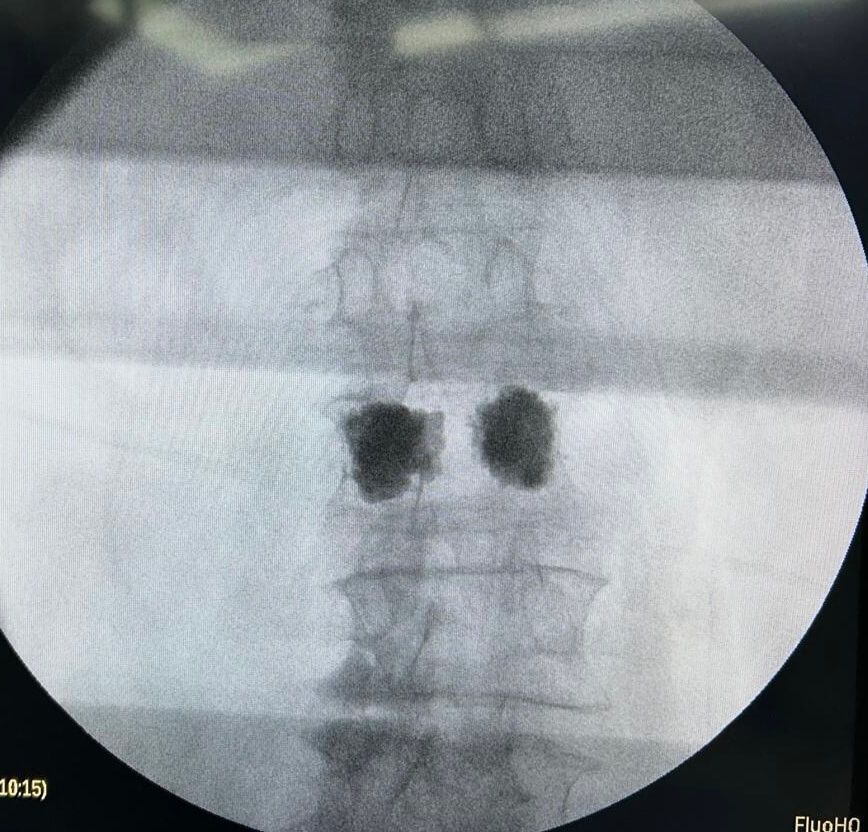

Cirugía de mínima invasión de columna vertebral

Realiza cirugías endoscópicas mínimamente invasivas de columna.

Cirugía de Columna

Realiza cirugía habitual y endoscópica mínimamente invasiva de columna vertebral.